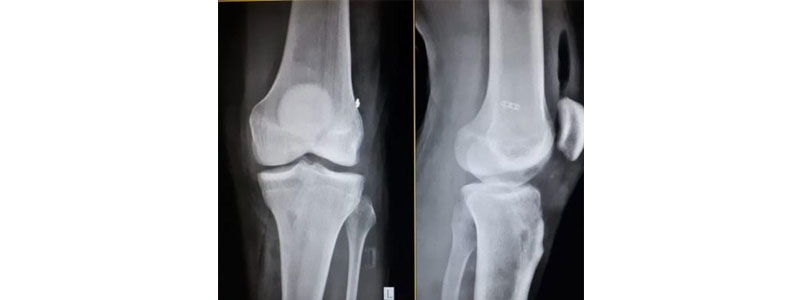

Arthroscopic Surgeon in Thane, Diagnosing joint wounds and infection starts with an exhaustive clinical history, actual assessment, and typically X-beams. Extra tests like MRI, or CT check additionally might be required. Through the arthroscope, a last finding is made which might be more precise than through "open" medical procedure, X-beam studies or MRI alone. Illness and wounds can harm bones, ligament, tendons, muscles and ligaments. The absolute most regular circumstances found during arthroscopic assessment of joints are:

Knee - meniscal (tendon) tears, chondromalacia (wearing or injury of cartilage cushion), and front cruciate tendon tears with unsteadiness.

Knee arthroscopy is an insignificantly intrusive technique that permits admittance to and treatment of wounds influencing the different designs of the knee joint. As per Arthroscopic Surgeon in Thane, few little cuts of under a centimeter are made to permit admittance to knee joint.

Knee arthroscopy is utilized to treat knee wounds. Perhaps the most widely recognized pathology is meniscus injury like clinical tear average or horizontal. Meniscal stitches and menisectomy (halfway or absolute) through knee arthroscopy are normal procedures for further developing security for the joint ligament.

Another normal issue is ligament injury (chondropathy, osteoarthritis or osteochondritis). Protecting the ligament will likewise safeguard the joint, hence forestalling wear of the knee.